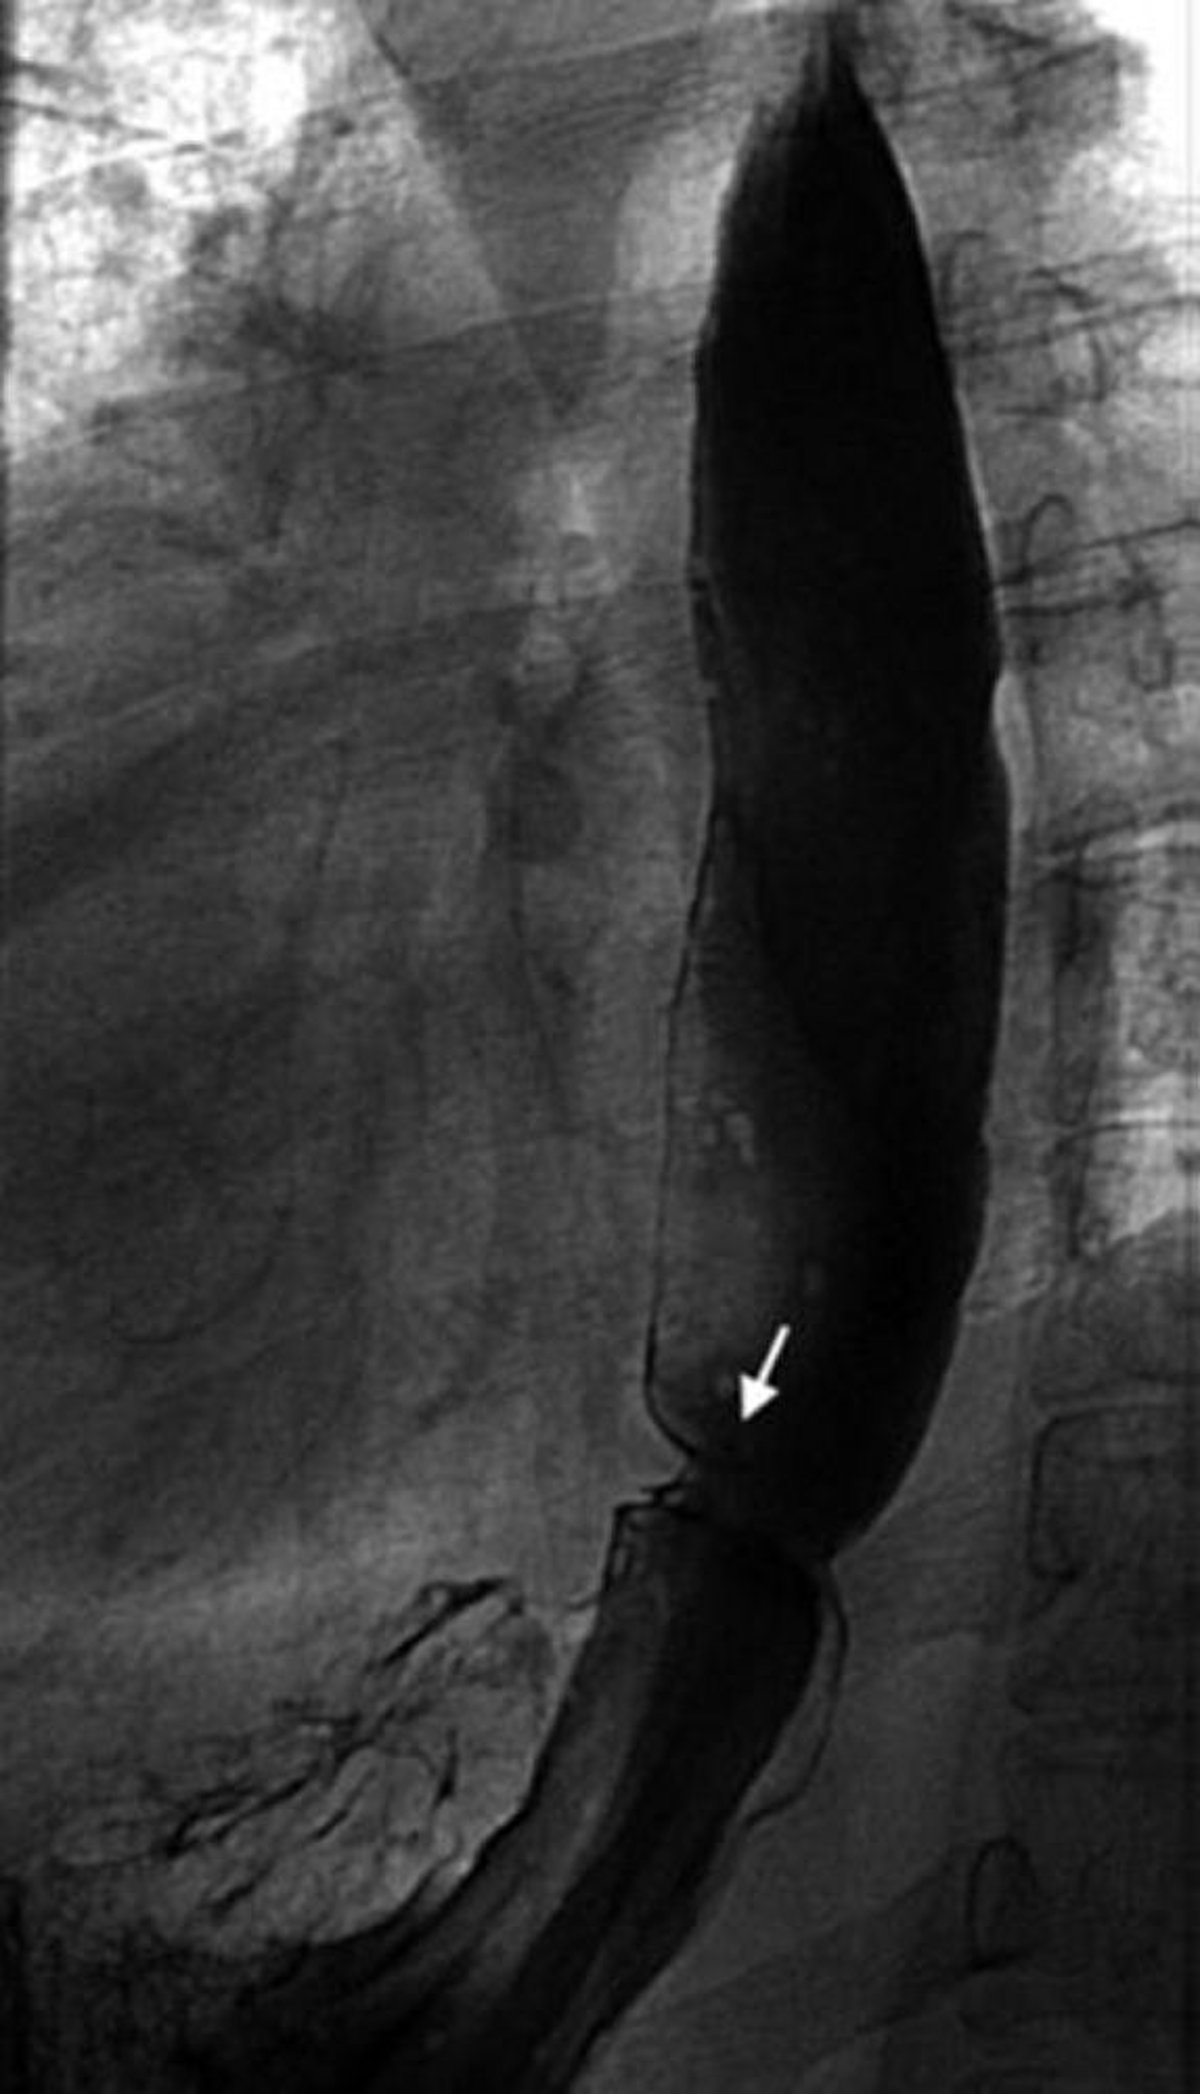

Transit baryté montrant un anneau œsophagien

Cette image montre un anneau de Schatzki (flèche).